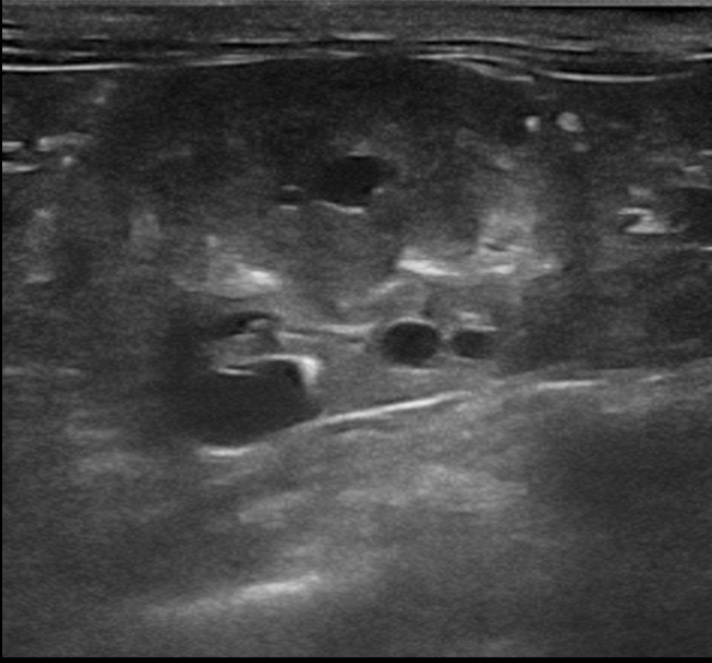

На УЗИ видны маленькие, но заметные кисты в почки

1. Ультразвуковое исследование (УЗИ) — это «золотой стандарт» прижизненной диагностики. Это безопасный и высокоинформативный метод. Опытный специалист может обнаружить характерные кисты в почках уже у котят в возрасте 8-10 недель, хотя для окончательного исключения заболевания рекомендуется проводить исследование после 10-месячного возраста, когда кисты становятся более очевидными.